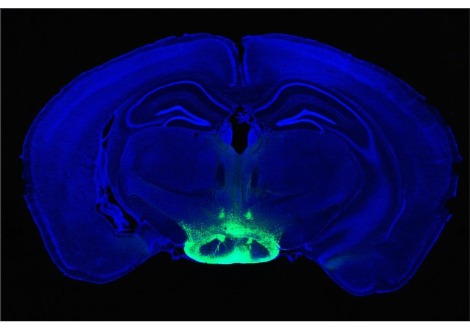

تعمل المُقترنات المشعة عن طريق توصيل نظير مشع قاتل للسرطان مع عامل استهداف يبحث عن الخلايا السرطانية ، كما كتب المحرر المساعد لي كريتش بورنر. يتكون الاتحاد من أربعة أجزاء : نظير مشع ، ومركب استهداف ، وسلة واقية للاحتفاظ بالنظير ، ورابط لتثبيت جميع الأجزاء معًا . ومع ذلك ، فإن تطوير هذه الأدوية يطرح العديد من التحديات . يجب تصميم المكونات للعمل معًا لاستهداف الورم وعدم إتلاف أجزاء أخرى من الجسم . اختيار النظائر المشعة الصحيحة هو أيضا مفتاح ؛ تركز الشركات حاليًا على نوعين من النظائر ، بواعث ألفا وبواعث بيتا ، لكل منها مزاياها وعيوبها . يمكن أن يتسبب العرض المحدود للمكونات المشعة الضرورية أيضًا في حدوث مشكلات ، حيث لا يمكن الحصول على هذه النظائر إلا من المولدات أو السيكلوترونات أو المفاعلات النووية أو النفايات المشعة القديمة .